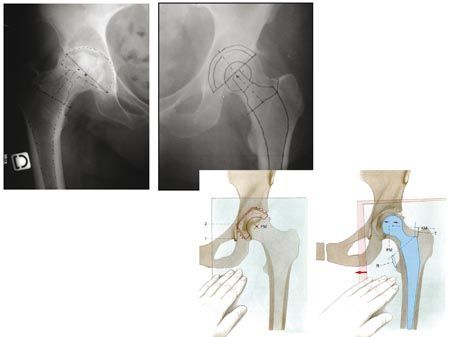

Actualité Planification informatique d'une prothèse totale de hanche - Intérêts dans l'utilisation d'une prothèse à col modulaire , Gilles Pasquier Service de Chirurgie orthopédique, CHU de Lille, 59037 Lille, France 🖂 gilles.pasquier@chu-lille.fr , A. Mouttet Polyclinique St Roch, 66330 Perpignan , E. Durante Avenue des Sciences, Yverdon les Bains, CH-1400 , J. Plé Avenue des Sciences, Yverdon les Bains, CH-1400 , Elhadi Sari-Ali Hôpital de la Pitié-Salpêtrière, Boulevard de l’hôpital, 75013 Paris, France N°188 - Novembre 2009 ● 21 min de lecture